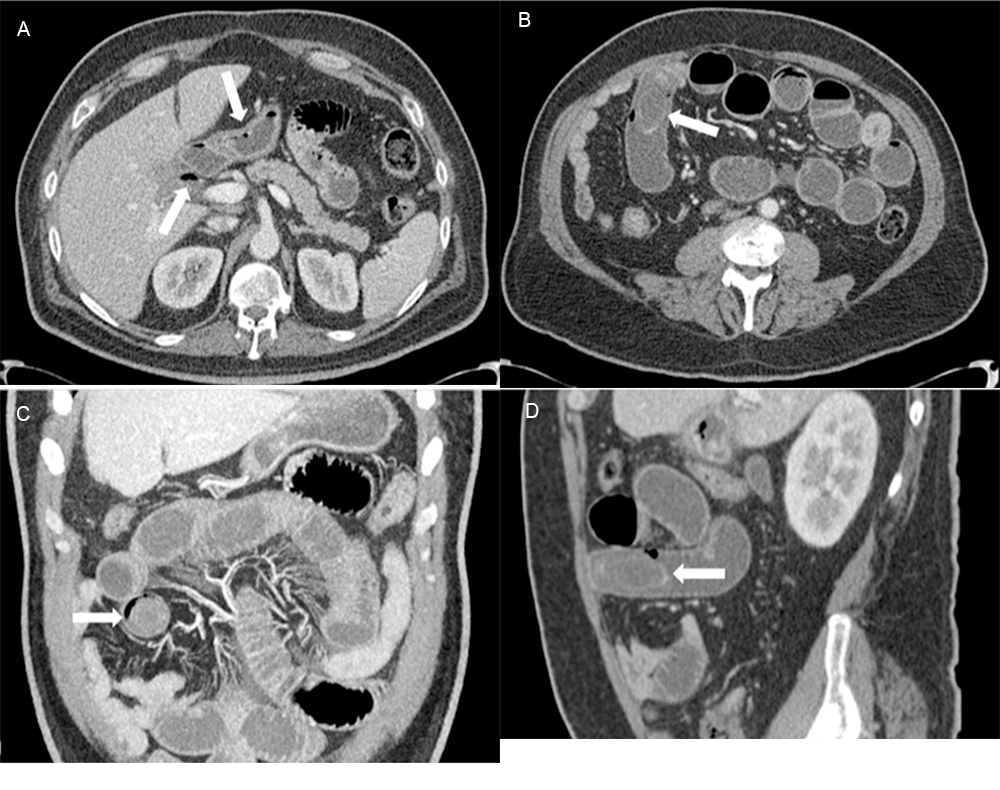

Plain abdominal Xray showing an obstruction and dilated intestinal Gallstones Post Gastric Sleeve — in line with recent available evidence, our results on the incidence of symptomatic gallstones after bariatric. pure restrictive procedures such as sleeve gastrectomy and gastric banding theoretically should result in less. • 95.8% of gallstone formers developed. — gallstones are common after rapid weight loss after sleeve gastrectomy. A multivariate analysis of risk factors. —. Gallstones Post Gastric Sleeve.